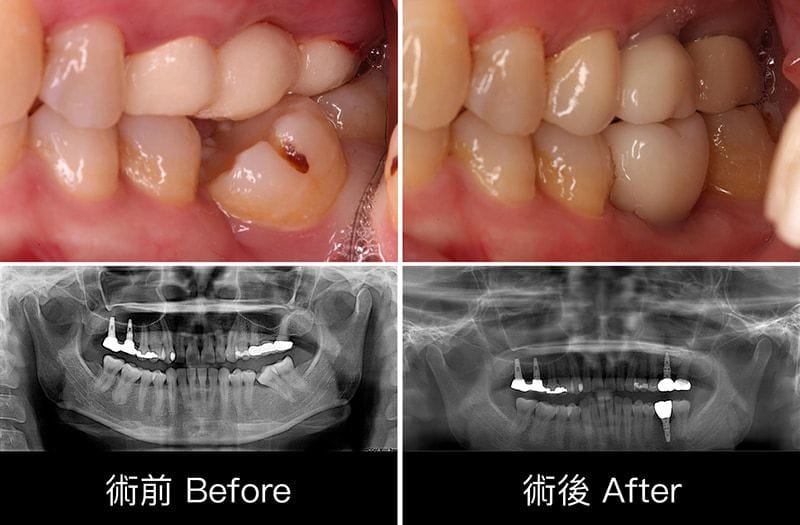

我們等待上顎半年、下顎三個月人工植牙骨整合的時間後,順利地把正式假牙完成。

圖示:植牙完成後裝上正式假牙的X光片 圖示:鼻竇增高術、補骨與植牙手術後,人工植體周圍骨頭狀況穩定

圖示:牙周病治療與手術的前後比較

Miss Feng目前已經恢復齒列完整,可以放心地享受美食了,但還是建議每天多花幾分鐘做好口腔衛生,定期至牙醫做全口檢查喔!